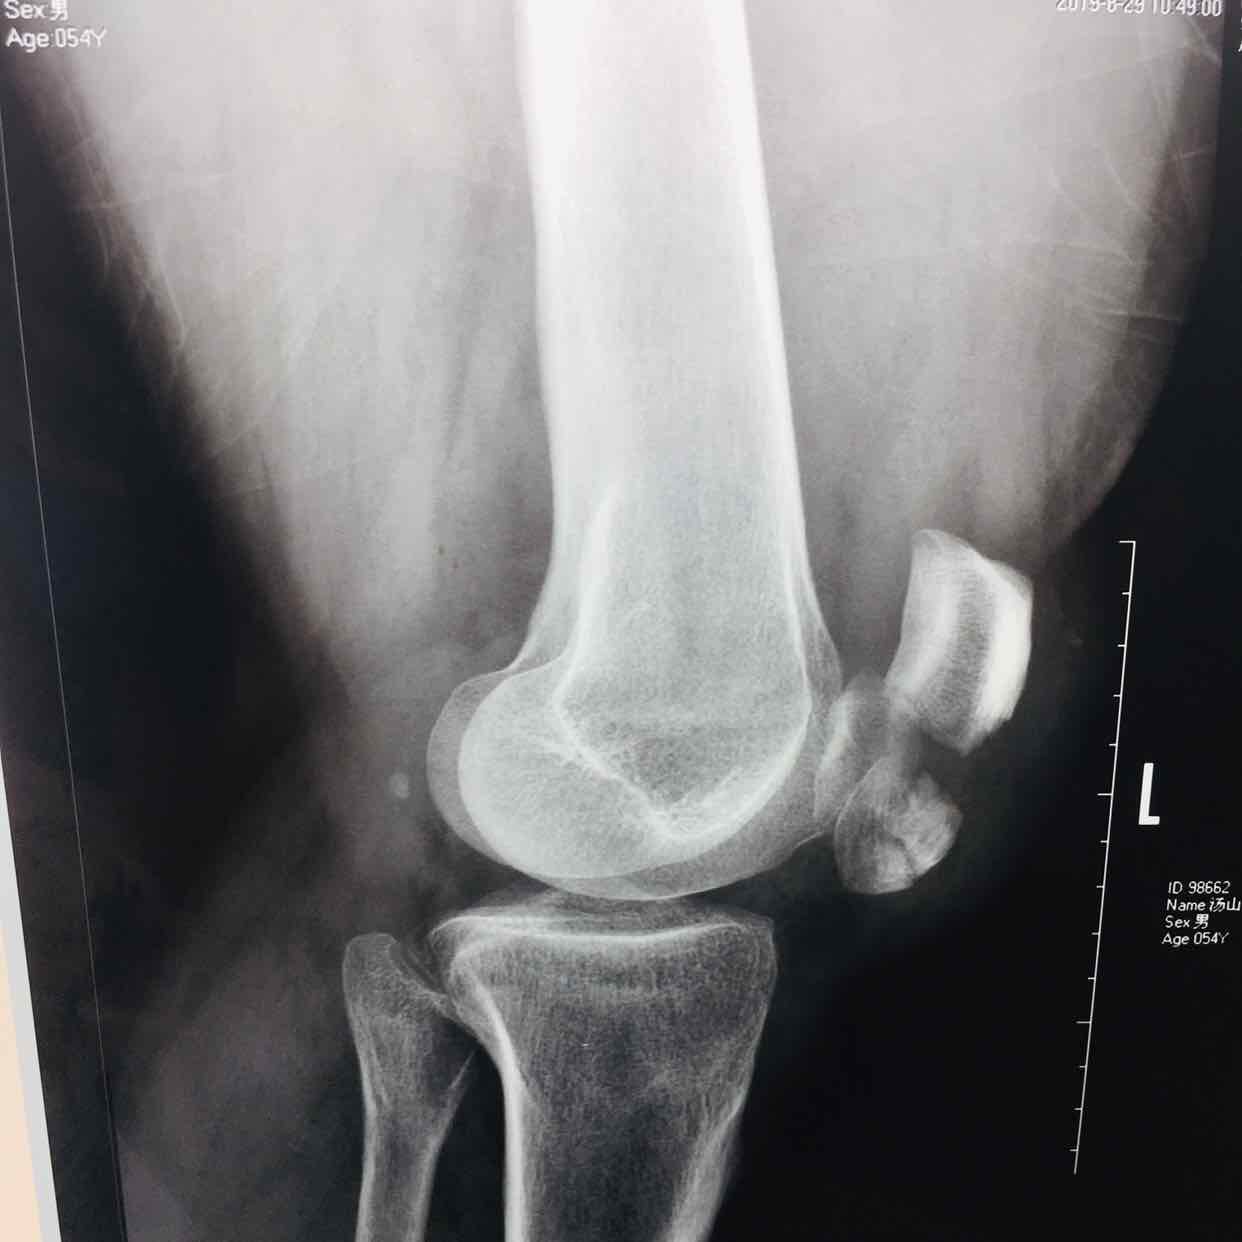

髌骨粉碎性骨折(髌骨爪➕克氏针固定)

摔伤后左膝部肿痛,活动受限1小时入院。既往身体健康,无特殊不良嗜好。

生命体征平稳,心肺复未见异常。左膝部肿胀明显,皮色发红,皮温高,压痛明显,可及骨折断端,伸膝关节受限,末梢血运感觉正常。

诊断左髌骨粉碎性骨折在腰麻下行切复内固定术,术后抗炎,消肿止痛等处理。